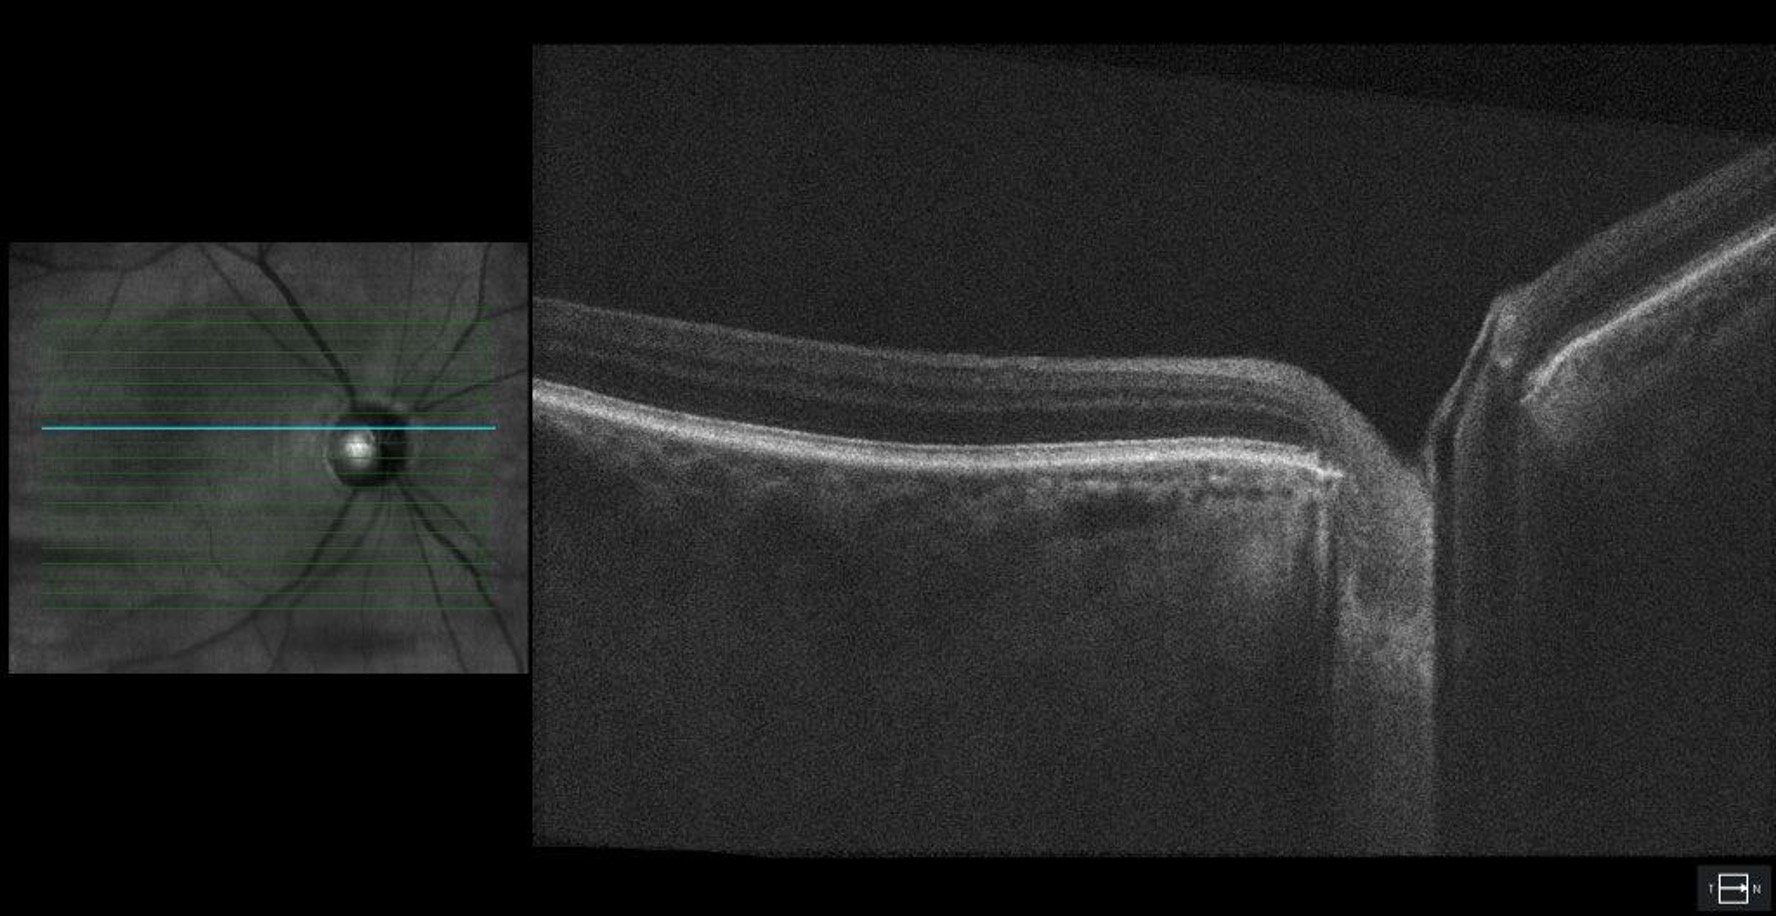

Figure 3. Optical coherence tomography (OCT) of the optic nerve head. Reduced retinal nerve fiber layer (RNFL) thickness in both eyes with an average RNFL thickness of 70 μm OD and 70 μm OS.

Optical coherence tomography (OCT) of the optic nerve head showing severe dropout of the ganglion cell complex (GCC) in both eyes. Average GCL thickness was 53 μm OD and 55 μm OS.

Figure 4. Optical coherence tomography (OCT) of the optic nerve head showing severe dropout of the ganglion cell complex (GCC) in both eyes. Average GCL thickness was 53 μm OD and 55 μm OS.